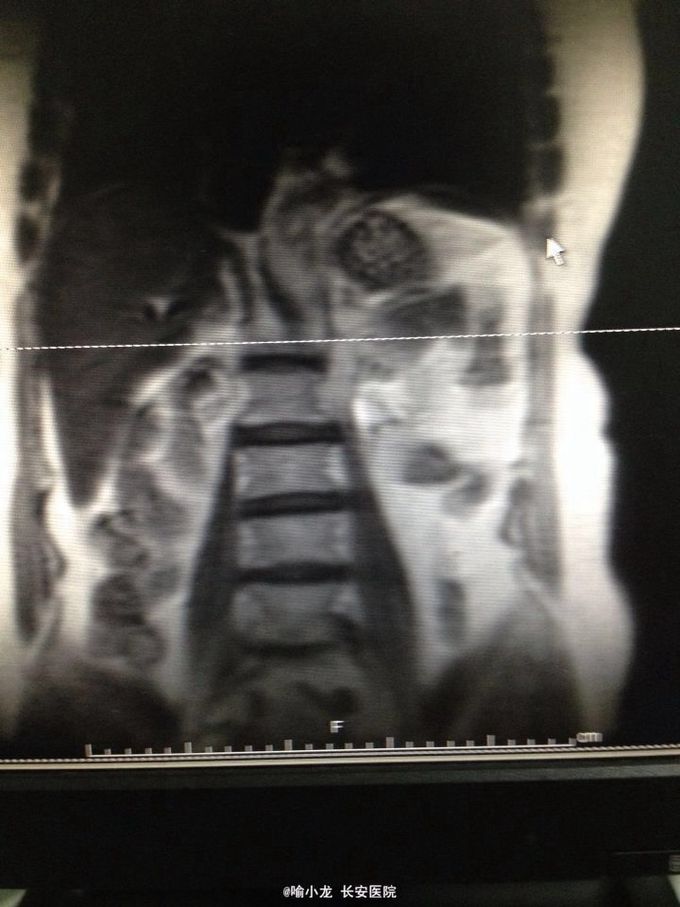

入院查血常规、肝肾功能、电解质、血脂六项、凝血四项、肿瘤四项、粪常规均基本正常;尿液分析示潜血3+,白细胞+;入院留48小时尿培养阴性;血型鉴定B型,血气分析、输血前四项基本正常;心电图、心脏彩超、腹部彩超、胸片及胸部CT检查均大致正常;下腹部+盆腔CT示左侧肾盂伴左侧输尿管全程扩张,右侧肾囊肿大小约2.0cmx1.3cm;泌尿系水成像示右肾囊肿约1.4cm,左侧输尿管上段内见条形低信号影。初步诊断:1.左侧输尿管肿瘤;2.左侧肾盂积水;3.右侧肾囊肿;4.泌尿系感染;5.高血压3级。入院后抗感染、止血对症治疗后,阵发性血尿无缓解,出现左侧肾绞痛伴发热乏力,遂急诊行膀胱镜检查并置入输尿管导管,术后阵法性血尿仍不缓解,2天后在静脉全麻下急诊行膀胱输尿管镜检查+左侧双J管置入术,术后间断寒战发热,最高体温39℃,化验尿培养示大肠埃希氏菌,病检示左输尿管高级别乳头状尿路上皮癌,根据药敏抗感染疗5天后,体温渐恢复并稳定,4天后在全麻下行左侧肾脏输尿管根治性切除术,术后病理示输尿管中段高级别乳头状尿路上皮癌局灶侵及固有层,外膜未见癌侵润,术后恢复良好。